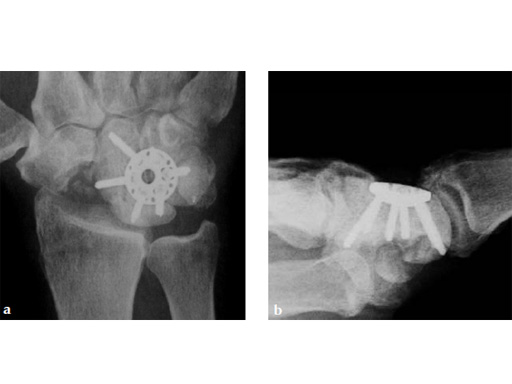

Fig 1ab Preoperative x-rays. Notice the midcarpal joint destruction and the DISI deformity of the lunate.